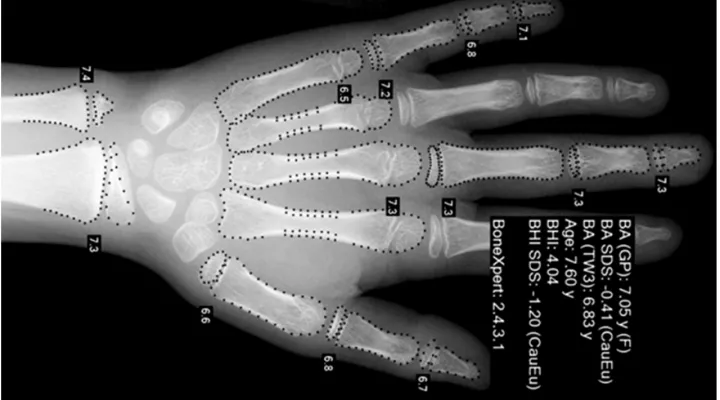

Kinderhände automatisch vermessen

In Zusammenarbeit mit einem dänischen Forschungsteam wurde mithilfe der Handröntgenbilder der ZLS ein Computerprogramm (BoneXpert®) entwickelt.

Dieses vermisst Röntgenbilder von Kinderhänden nun automatisch und unterstützt damit die zuverlässige Diagnose von Wachstumsstörungen. Das Programm wird heute im Kinderspital Zürich wie auch in vielen anderen Kliniken weltweit eingesetzt.